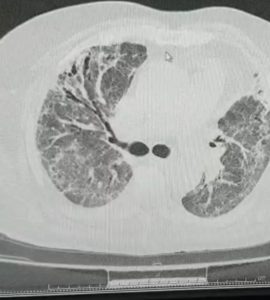

Examinare CT la o lună după internarea în secția de pneumologie post COVID. Leziunile pulmonare au caracter evolutiv spre fibrozare, cu bronsiectazii retractile prin fibroze pleurale, cu aspect de figure de miere în zonele subpleurale (aspect lezional imagistic similar fibrozei pulmonare).